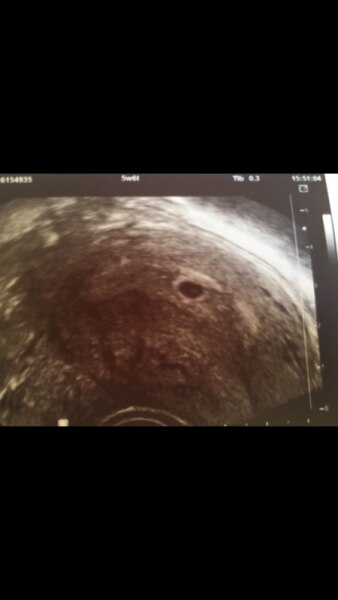

...ist nun rund und man konnte schon den dottersack und laut der bereitschaftsärztin ein bisschen Baby sehen :-) leider ist das Ultraschallgerät schon etwas in die Jahre gekommen Mein Eisprung war ja ziemlich verspätet deswegen ist es gerade nicht sicher ob ich 5+6 oder 5+3 bin.

Bild zu Die unrunde fruchtblase... - Forum für März - Mamis